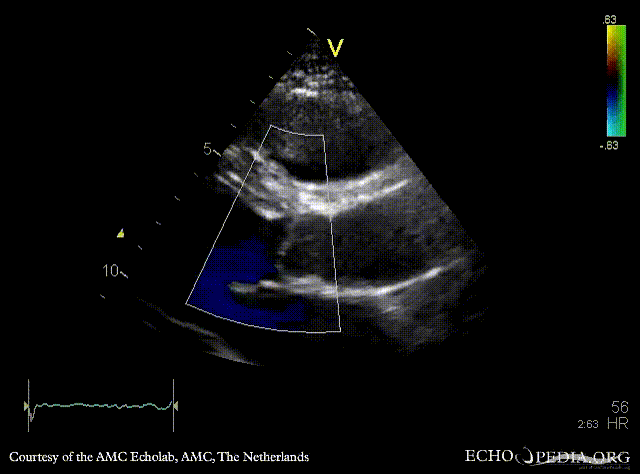

Davids procedure

Courtesy of: AMC Echolab, AMC, The Netherlands

PSAX: native aortic valve and prosthesis in ascending aorta PSAX with Color Doppler